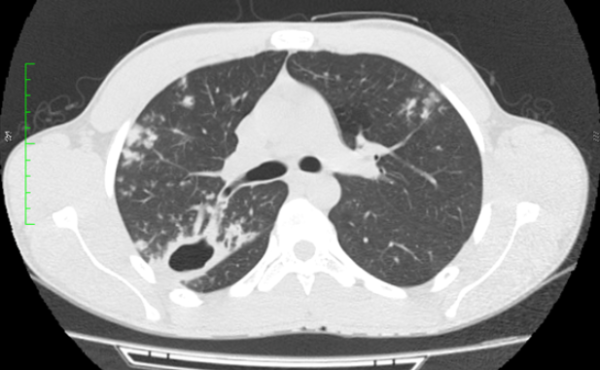

Paciente sexo masculino, 18 anos, sem comorbidades, com quadro arrastado de febre e perda ponderal há cerca de três meses. Foi realizado radiografia de tórax (não disponibilizada), com laudo inconclusivo. Optou-se por prosseguir investigação com tomografia computadorizada do tórax.

Diante das imagens, qual a melhor descrição e a principal hipótese diagnóstica?

CEscavação de paredes espessadas no lobo superior direito e nódulos com distribuição centrolobular dispersos pelo parênquima – tuberculose